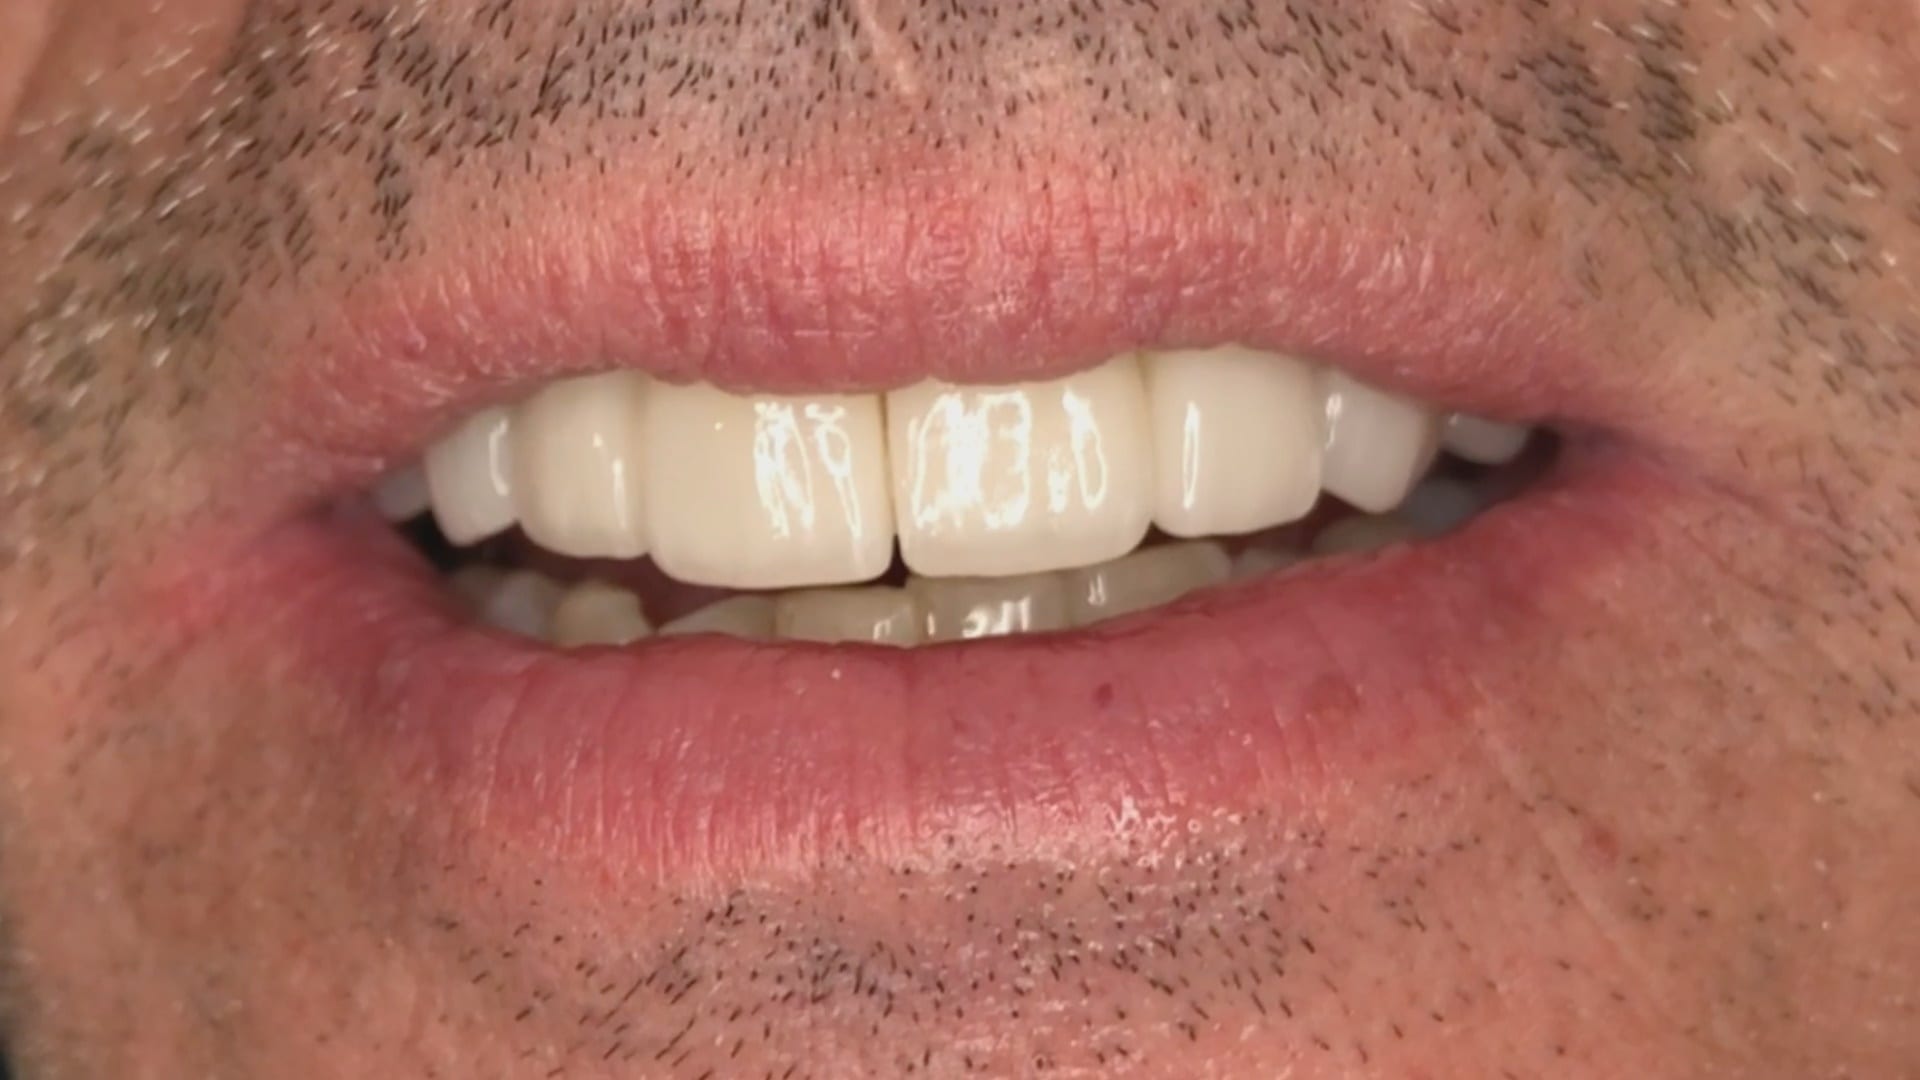

Immediate Post Op